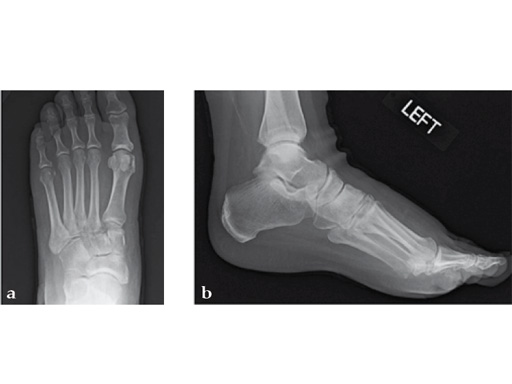

Case 8: VA -locking X-plate

A 38-year-old man fell from a 7-foot height while at work. The patient was seen at an urgent care facility and diagnosed with an ankle sprain. He was placed in a stirrup brace and instructed to bear weight as tolerated.

After 4 months the patient presented for a second opinion. His complaint was pain to the lateral column and subtalar joint. The preoperative lateral x-ray is notable for a malunited talar neck fracture with subluxation of the subtalar joint. The disproportion of the medial and lateral columns and a cavovarus position of the foot are seen on both the AP and lateral views. The degenerative changes at both the talonavicular and subtalar joints are significant.

The patient was treated with arthrodesis of the talonavicular and subtalar joints. The compression/ distraction device was used to restore the length of the medial column. The articular surface of the subtalar joint was prepared arthroscopically. The talonavicular joint was debrided then packed with a tricalcium matrix. Length was maintained using a locking X-plate. The subtalar joint was then fixed with a 6.5 mm headless compression screw.

The patient returned to work 3 months after surgery. He wears an ankle brace when on uneven surfaces. His lateral column and subtalar pain have resolved.